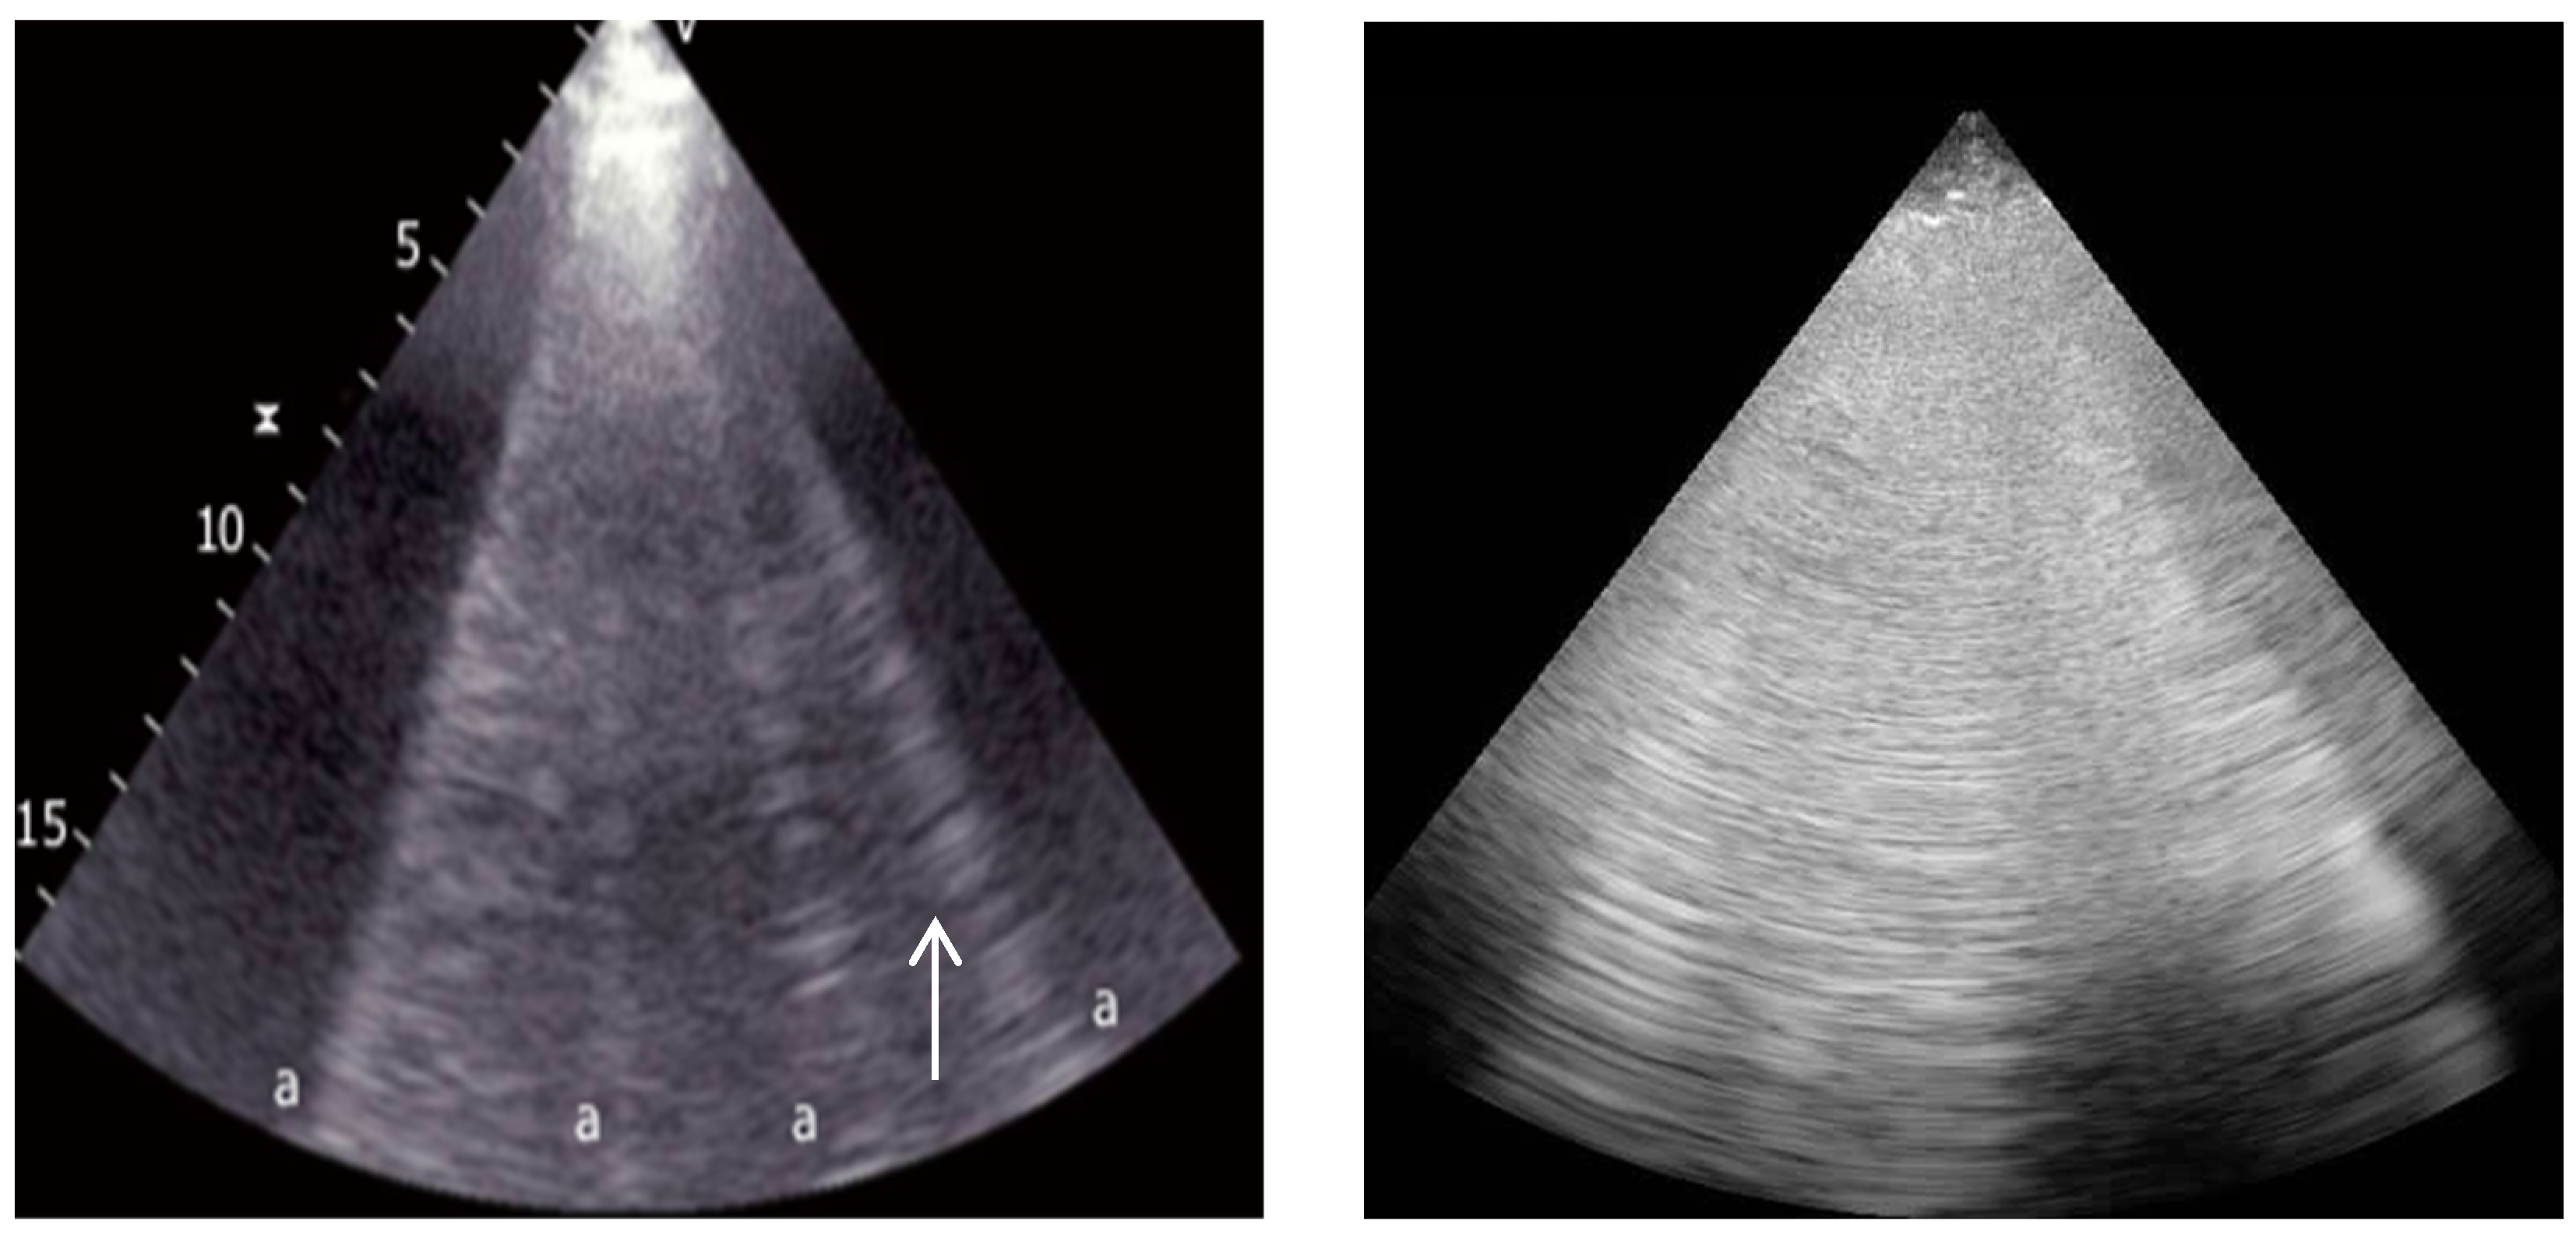

4.3. Point-of-Care Venous Doppler Ultrasound

4.3.1. Inferior Vena Cava

4.3.2. Hepatic Vein Flow

4.3.3. Portal Vein Flow

4.3.4. Intrarenal Vein Flow